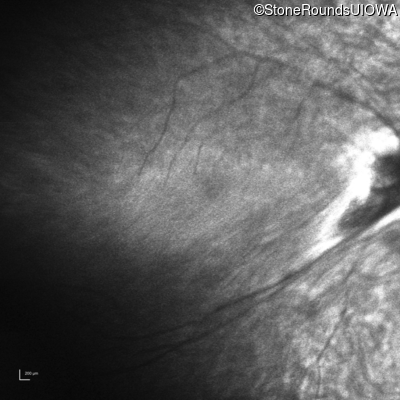

Infrared Fundus Photograph - Right - Light Perception

Exemplar